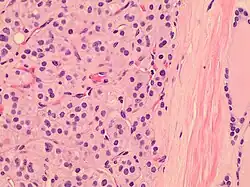

Histopathology of a Hürthle cell adenoma

Hürthle cells are characterized as enlarged epithelial cells. These cells, when stained with hematoxylin-eosin show as pink. This is due to the abundant mitochondria and granular eosinophilic matter within the cells' cytoplasm. These cells are often found in the thyroid. The thyroid is a butterfly-shaped organ, responsible for producing various hormones for metabolism. These cells are often benign, but they can be malignant and metastasize. Hürthle cells are resistant to radiation, but can be treated using radioactive iodine treatment.[4]